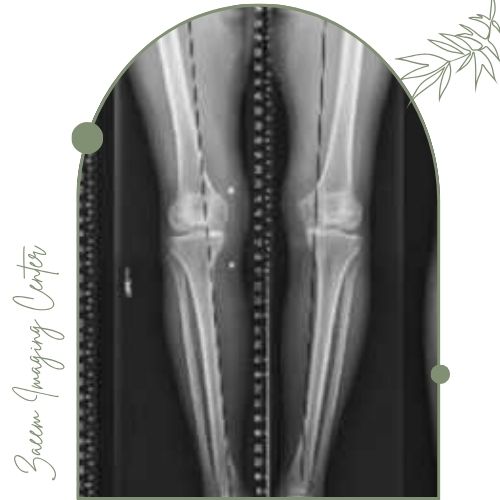

رادیوگرافی الایمنت ویو برای ارزیابی دقیق وضعیت ستون فقرات، زانو و استخوانها در حالت ایستاده